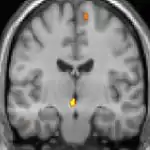

![]() | ![]() | ![]() |

| Positron emission tomography (PET) shows brain areas being activated during pain. | ||

Positron emission tomography (PET) scans indicate the brain areas which are activated during attack only, compared to pain free periods. These pictures show brain areas that are active during pain in yellow/orange color (called "pain matrix"). The area in the center (in all three views) is specifically activated during CH only. The bottom row voxel-based morphometry (VBM) shows structural brain differences between individuals with and without CH; only a portion of the hypothalamus is different.[36]